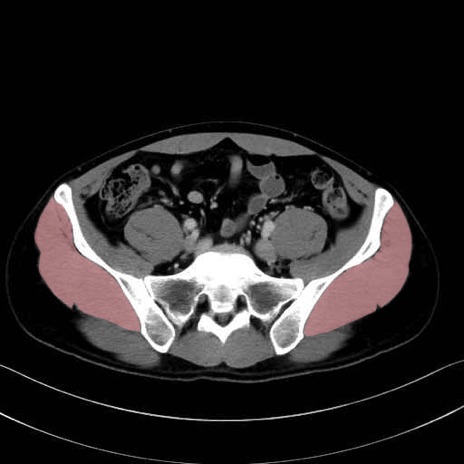

中殿筋 (Gluteus medius)